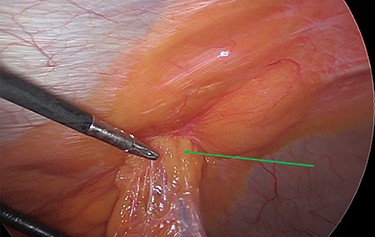

The viable omentum was reduced into the peritoneal cavity. Two lipomas were then observed attached to the parietal peritoneum (Figs 3 and 4). The lipomas were also reduced into the peritoneal cavity from within the hernia sac. Each one was 2 cm in diameter based on laparoscopic visualization using the 1 cm markings on a suction irrigation device.

Reduction of the first peritoneal lipoma (green arrow) into the peritoneal cavity.